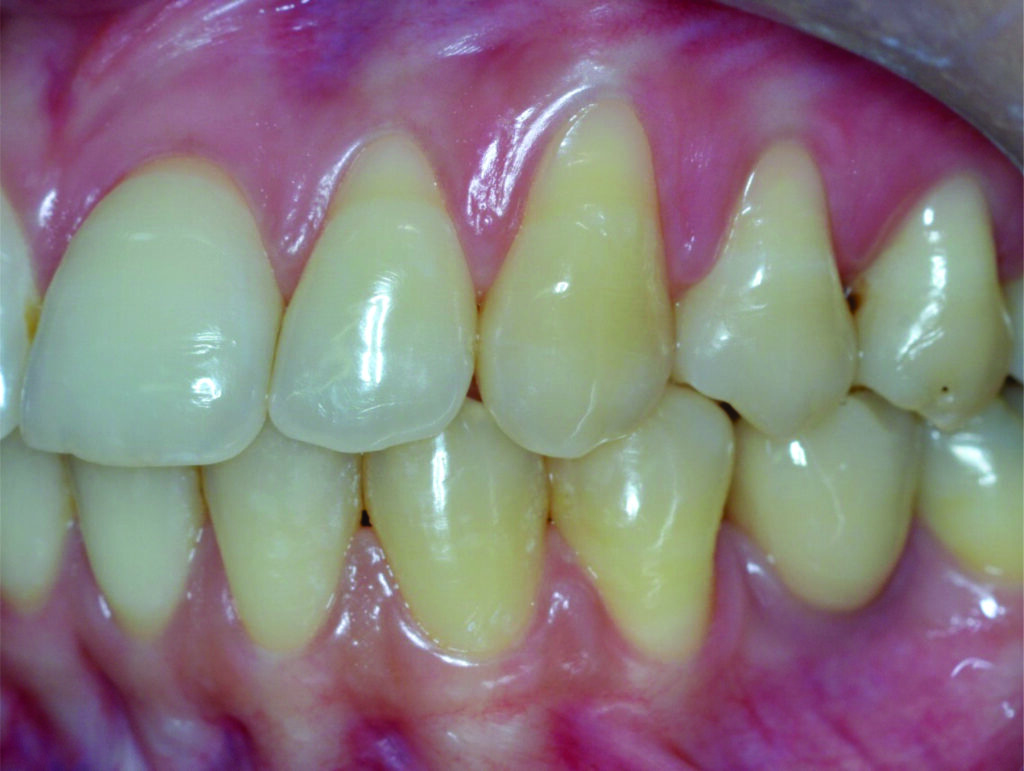

Retração ou Recessão Gengival é o que ocorre quando a margem gengival migra em direção apical (ponta da raiz) deixando raiz exposta.

O surgimento de uma Retração Gengival normalmente ocorre por uma interação de fatores, de forma que temos fatores predisponentes (ausência de Gengiva Queratinizada, má posição dentária, tração de freios e bridas, etc) e fatores desencadeantes (escovação traumática, Coroas desadaptadas, inflamação, trauma oclusal, fumo, etc).

Sinais e Sintomas

Pode ocorrer em um único dente;

Pode ocorrer em vários (Múltiplas)

Aspecto antiestético;

Maior facilidade de desenvolver cárie radicular;

Aumento da Sensibilidade a alterações de Temperatura.

Tratamento

O tratamento começa pela identificação da causa e sua eliminação. Feito isso, é necessária uma avaliação da necessidade, viabilidade e efetividade da terapia cirúrgica. Várias técnicas cirúrgicas foram descritas com a possibilidades de atingir um recobrimento muito satisfatório, tanto para retrações isoladas quanto para múltiplas, cabe ao Periodontista avaliar e decidir qual a melhor forma de atuação.